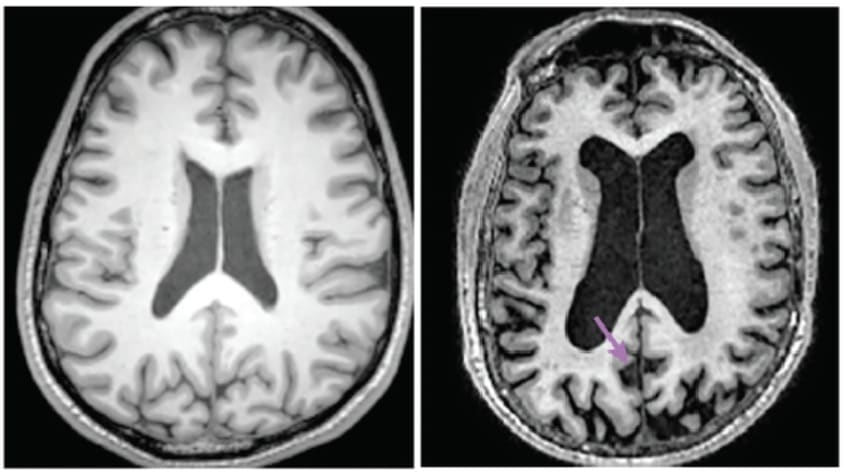

By the time patients with severe dementia actually die, their brains are catastrophically damaged. They typically show no signs of recognizing family members. They often haven’t responded meaningfully to their environment in months or years. Their brains are riddled with plaques and tangles. And they’ve lost 20-50% of their synaptic connections - so much that their brains have visibly shrunk on MRI scans.